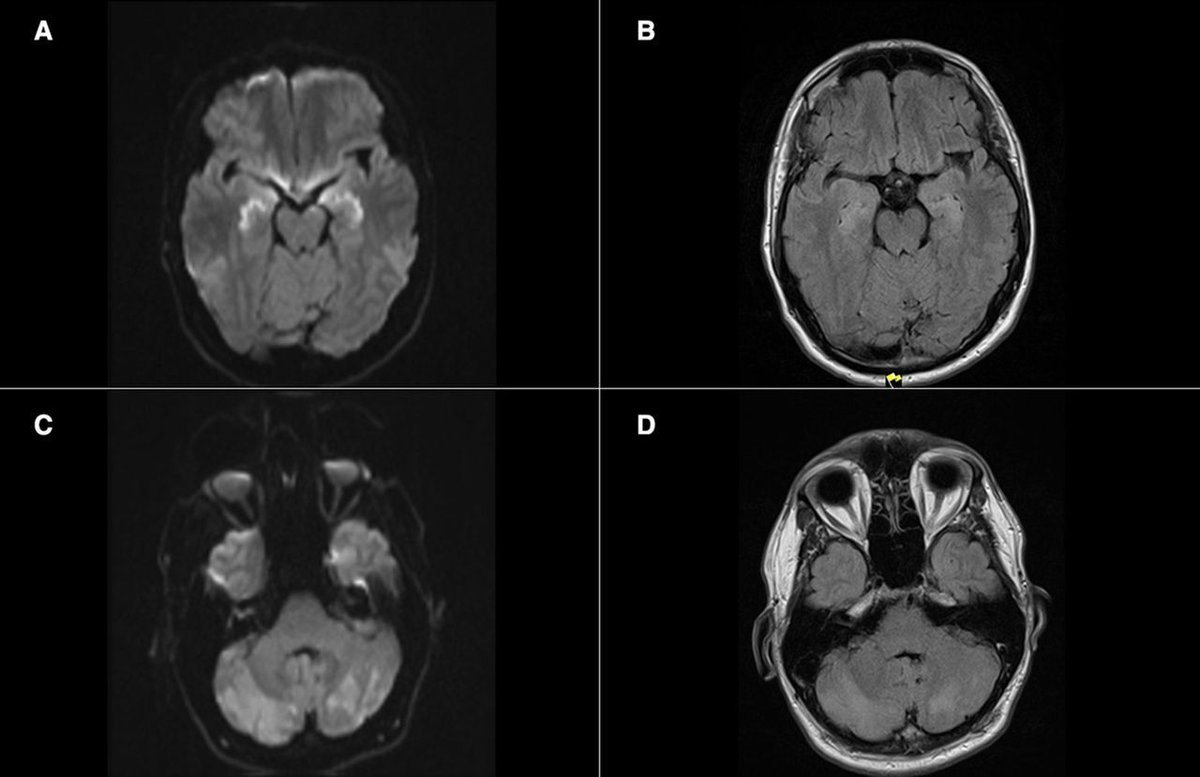

š§ Fentanyl misuse can cause CHANTER syndrome: Cerebellar, hippocampal and basal nuclei transient oedema with restricted diffusion. Thereās a characteristic MRI pattern: restricted diffusion in the basal ganglia and hippocampi, with cerebellar oedema and haemorrhage. š Open